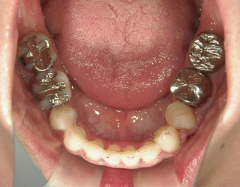

矯正歯科 治療後矯正歯科 全顎ワイヤー矯正 治療後矯正歯科(全顎ワイヤー矯正)治療後

全顎ワイヤー矯正 症例(18)

30歳女性 浜松市北区在住

治療期間3年4ヶ月

主訴:前歯の歯並びが気になる。

矯正歯科 治療後